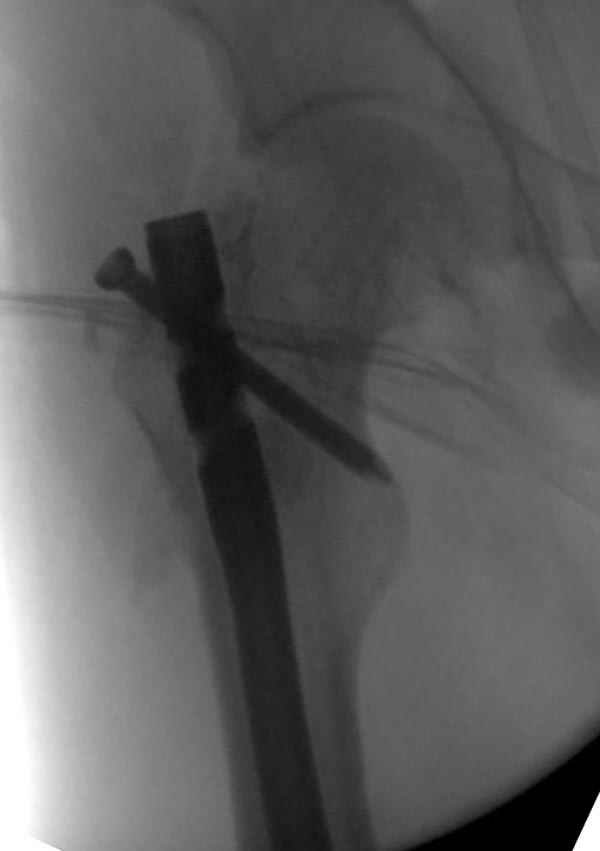

На следующий день произвели интрамедуллярный остеосинтез: этапы во время операции (рис №8, №9)

и последующих снимках (рис №10, 11, 12, 13) перелом сростается и передвигается с полной нагрузкой.

При обзоре причин перелома, на снимке №2 обнаружили, что один из стержней аппарата наружной фиксации проходил только через передний кортекальный слой, что создало стрессовую зону на бедре и в результате перелом из-за незначительной травмы.